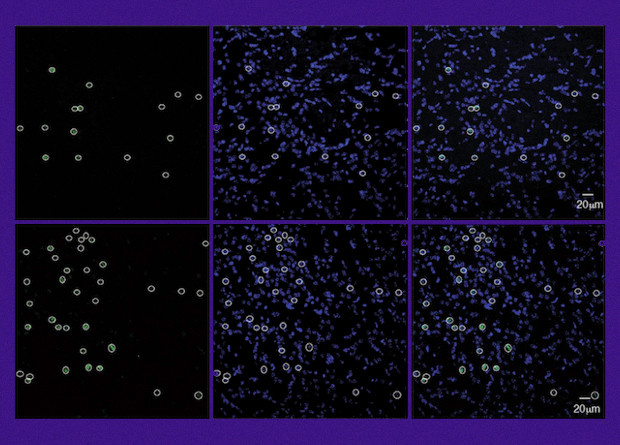

Исследователи из Школа медицины Икана Медицинского центра Маунт-Синай под руководством Аны Бадимон (Ana Badimon) обнаружили новую функцию микроглии: регуляцию нейронной активности по принципу отрицательной обратной связи. Ученые создали мутантные нейроны, которые несли рецепторы к клозапин-N-оксиду. Так нейроны можно активировать при помощи